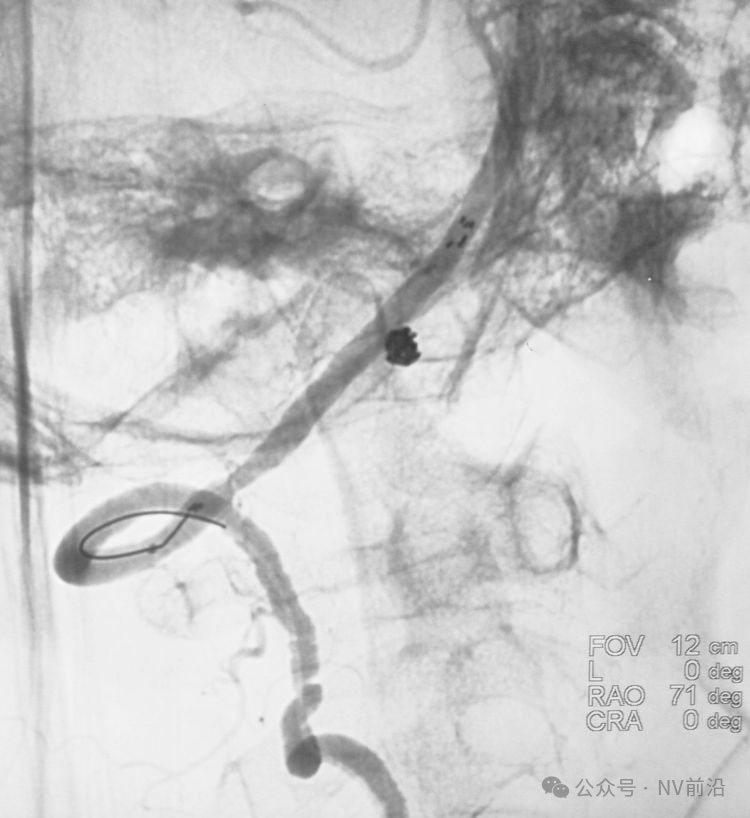

Solitaire 4×15支架(绿线)跨瘤颈半释放,压住微导管(红线)。

经微导管向瘤腔内送入首枚弹簧圈(QC-2-4-3D)。

继续送入两枚QC-1.5-2-Helix,完全栓塞动脉瘤,部分圈突入载瘤动脉。